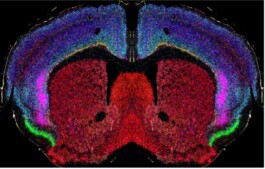

Les chercheurs étudient à la fois des approches non médicamenteuses, comme la stimulation cérébrale (tACS), et des pistes pharmacologiques ciblant une région clé du cerveau appelée le claustrum, impliquée dans la mémoire de travail. Grâce à des outils d’imagerie cérébrale de pointe et à des mesures en conditions réelles, ils cherchent à relier les mécanismes cérébraux observés chez l’animal et chez l’humain aux difficultés concrètes rencontrées au quotidien, comme l’isolement social ou les troubles de l’attention. L’objectif final est d’identifier des interventions sûres et efficaces pouvant être rapidement appliquées en clinique.

The project aims to better understand and improve cognitive functions such as memory and attention in people with psychopathological disorders, particularly those with 22q11.2 deletion syndrome. Researchers are exploring both non-drug approaches, like brain stimulation (tACS), and pharmacological strategies targeting a key brain region called the claustrum, which plays an important role in working memory. Using advanced brain imaging and real-life assessments, the team seeks to connect brain mechanisms observed in animals and humans with the everyday challenges these individuals face, such as social isolation and attention difficulties. The ultimate goal is to identify safe and effective interventions that can be rapidly translated into clinical practice.